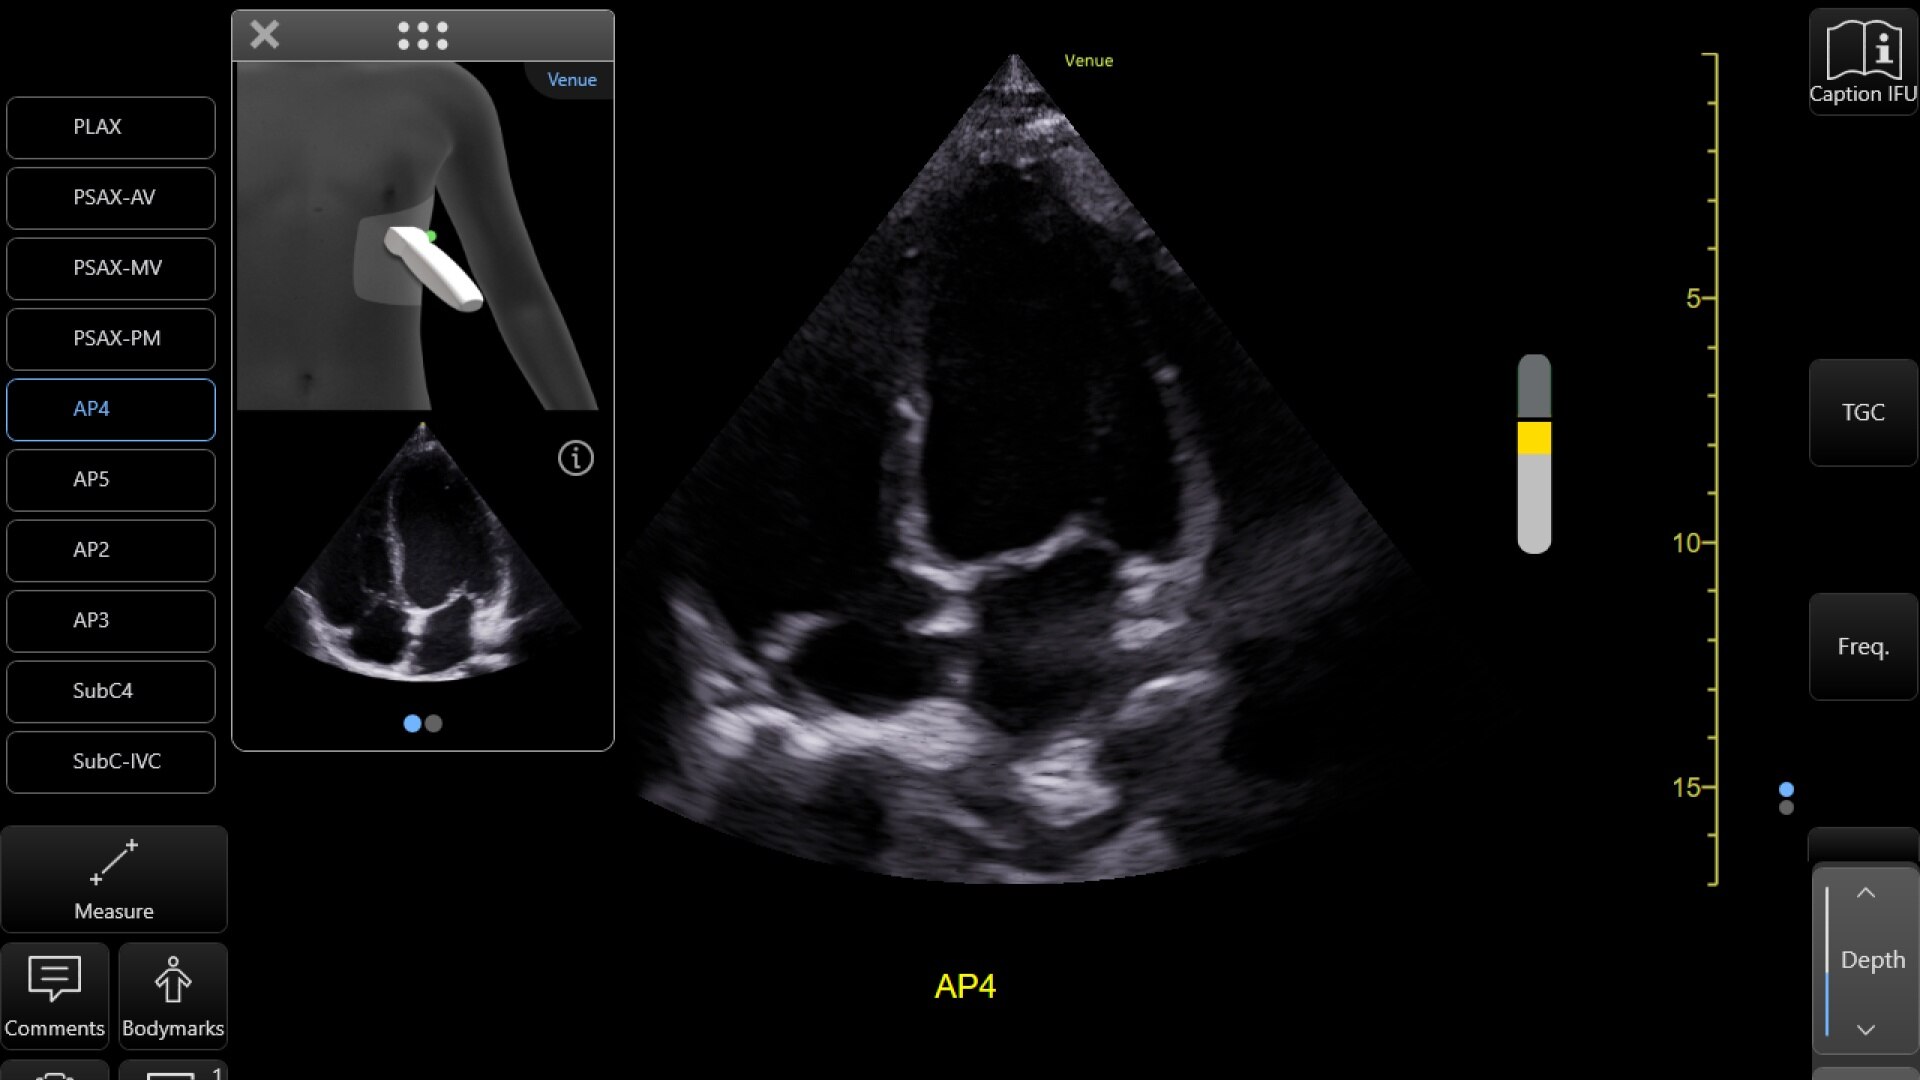

La información preliminar sobre la colocación de la sonda muestra dónde colocar y cómo orientar la sonda de ecografía. Al comenzar la exploración, se muestra una imagen de referencia de la imagen que está intentando adquirir.

Siga las instrucciones prescriptivas que aparecen en la pantalla. Mueva la sonda lentamente y observe cómo sube el medidor de calidad a medida que se acerca a una imagen de calidad diagnóstica.